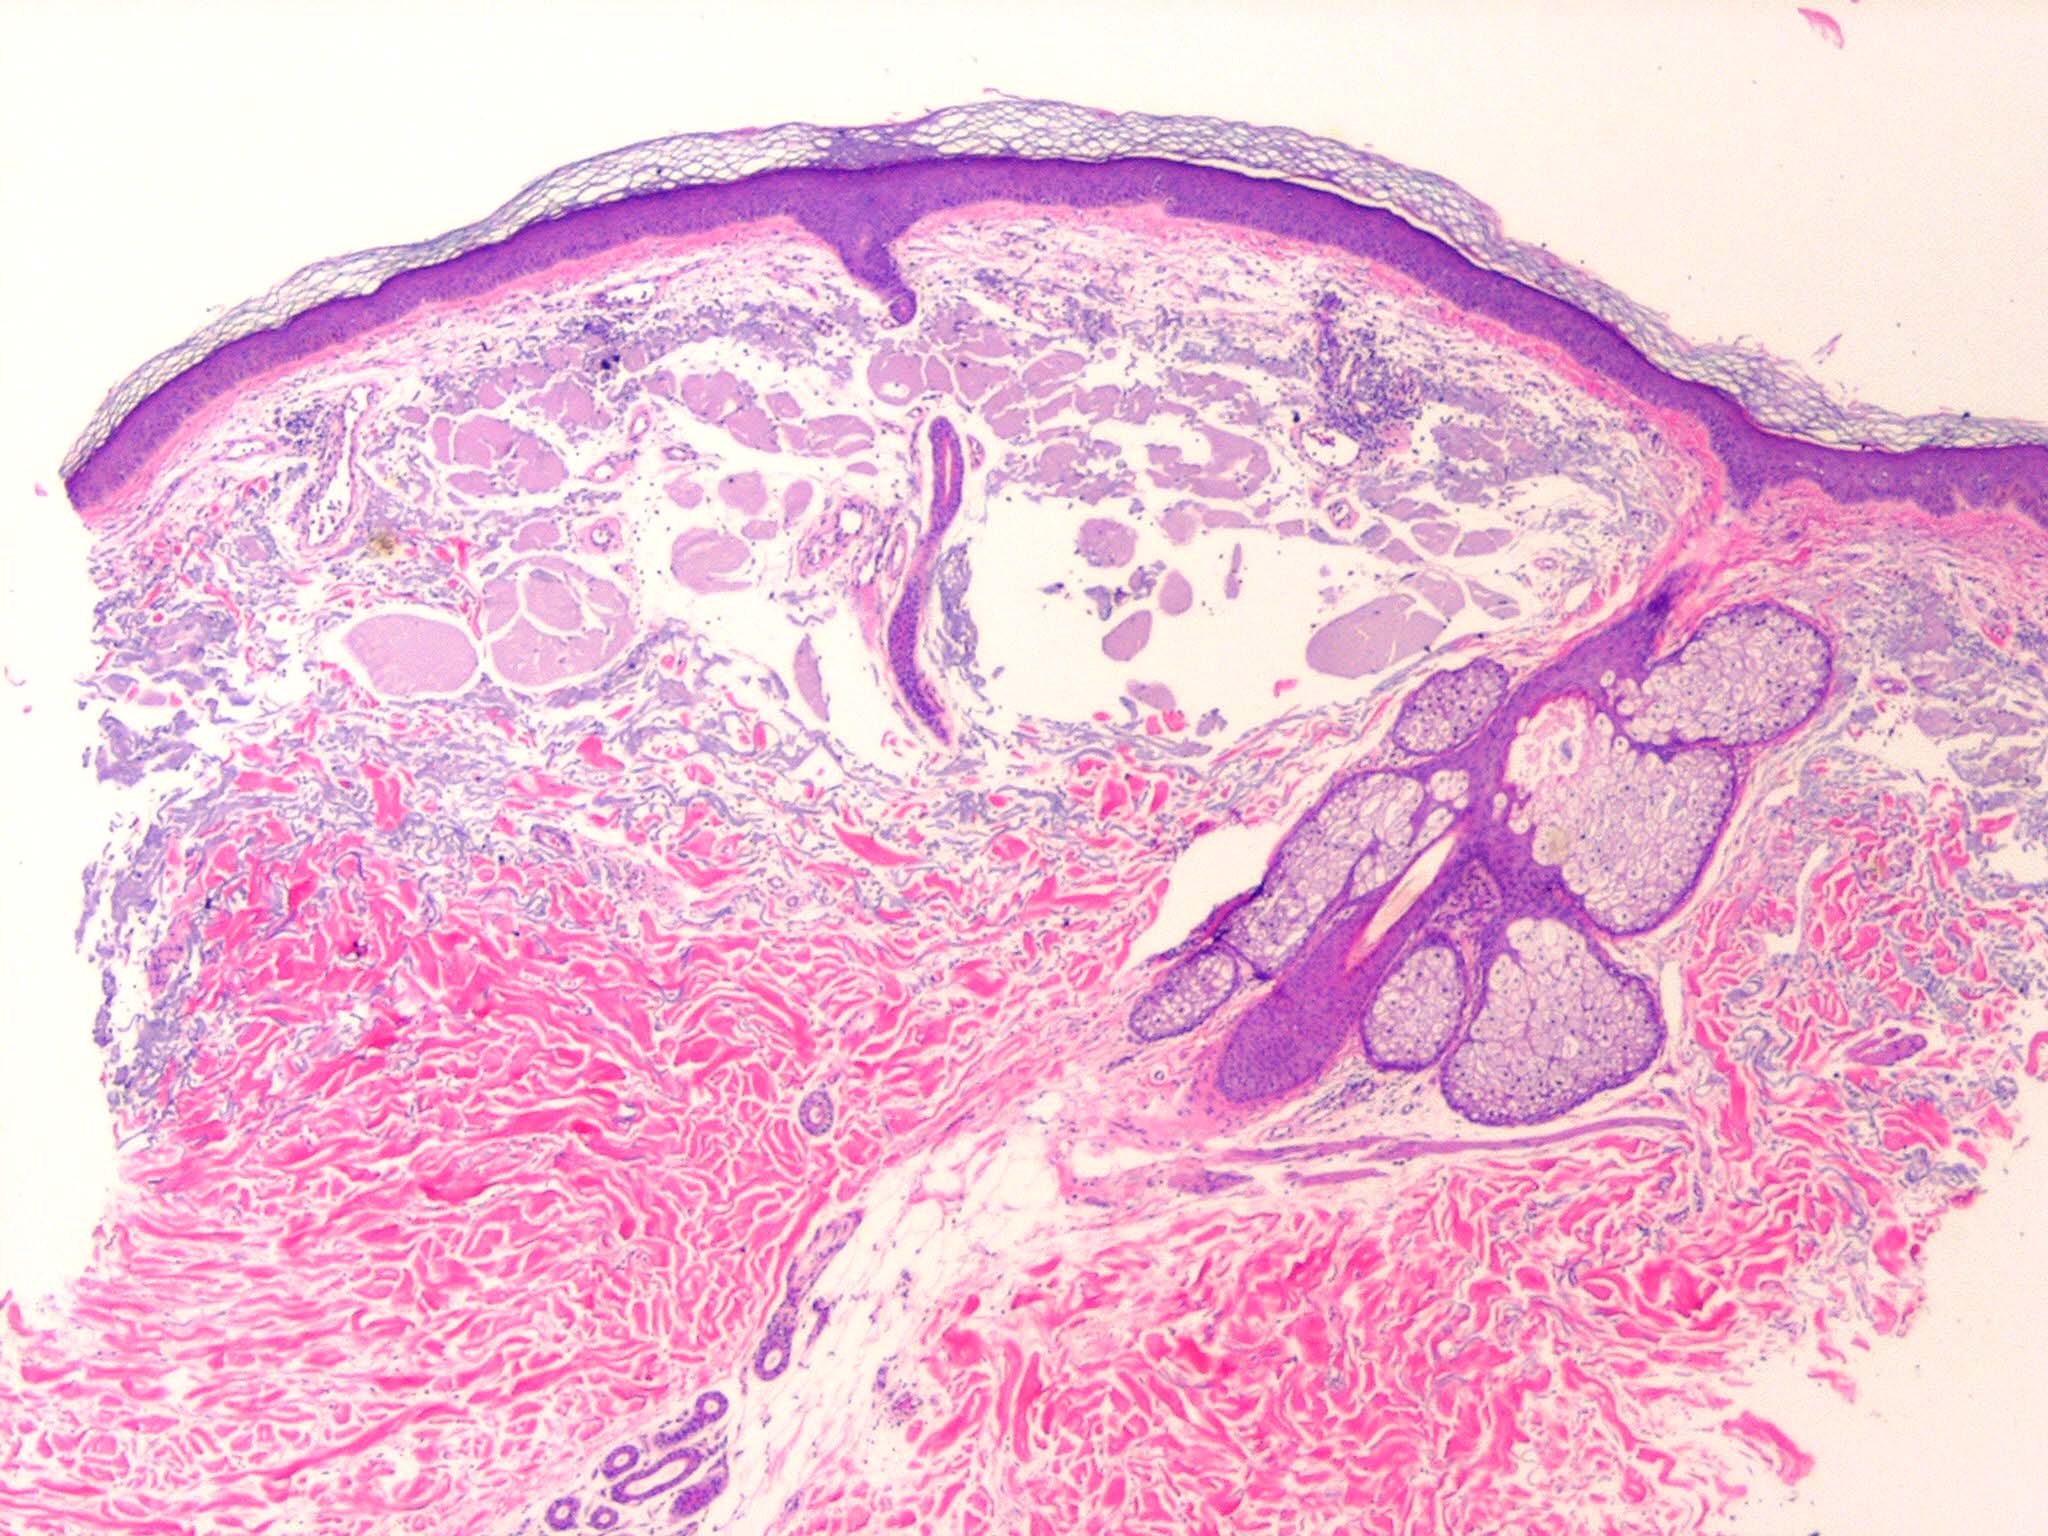

Colloid milium is a rare condition characterized by (1) the presence of multiple, dome-shaped, amber- or flesh-colored papules developing on light-exposed skin and (2) the observance of dermal colloid under light microscopy. The 4 variants are (1) an adult-onset type, (2) a nodular form (nodular colloid degeneration),1 (3) a juvenile form,2,3 and (4) a pigmented form, thought to be due to excess hydroquinone use for skin bleaching.4

Colloid milium is a degenerative condition linked to excessive sun exposure and possibly exposure to petroleum products and hydroquinone. The origin of the colloid deposition in the dermis is not certain, but it is thought to be due to degeneration of elastic fibers5,6 in the adult form and due to degeneration of UV-transformed keratinocytes in the juvenile form. Juvenile colloid milium is inherited.

• Skin lesions of colloid milium: Amber, waxy, partially translucent, firm papules occur in crops, ranging from 1-5 mm in diameter. Gelatinous material can be expressed. In the nodular form, larger nodules (5-10 mm) or plaques develop. The underlying skin may be thickened, furrowed, and hyperpigmented. In the pigmented form, the papules are gray-black and confluent or clustered.

• Skin distribution of colloid milium lesions: The lesions occur on light-exposed skin, with the cheeks, periorbital area, nose, ears, and neck most frequently involved; however, lesions may also occur on the backs of the hands and forearms. Nodules arising on one side of the face and the ipsilateral forearm have been described in a taxi cab driver. Upper eyelid margin involvement alone has been reported.7 Juvenile colloid milium may be associated with ligneous conjunctivitis or ligneous periodontitis. Rarely, lesions occur in the oral cavity.